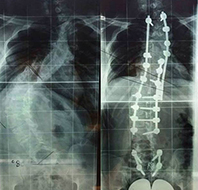

A veleszületett gerincferdülés tekintetében

Congenitalis scoliosis (veleszületett gerincferdülés) esetén a gyermekeket általában konzervatív úton (fűző, gyógytorna, egyéb fejlesztés) nem kezelik, ezek nem szükségesek (nem hatásosak). Dévény-torna, más terápia nem szükséges, hiszen ezek a csontos struktúrát nem befolyásolják. Alapvetően mindig a gerincsebész szakember egyénileg dönt a kezelésről. Érdemi kezelés (megfigyelés) a gyermek stabil állása után, egyéves kor körül kezdhető.

A kezelés menete, kezelési módok